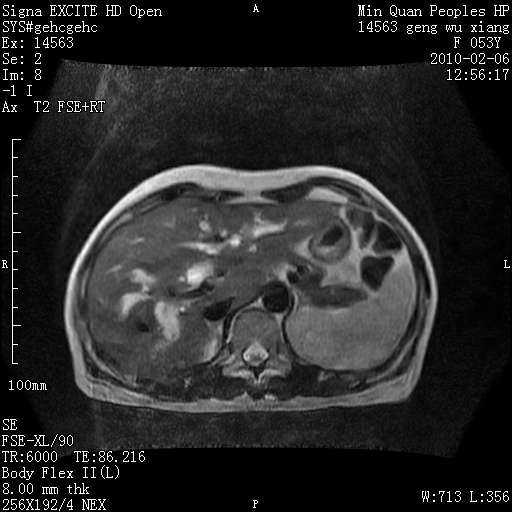

标题: MRI2762:胆道梗阻原因?

f,53y,全身黄染多日。

高位胆道梗阻 胆管癌可能性大

支持 高位胆道梗阻 胆管癌可能性大。